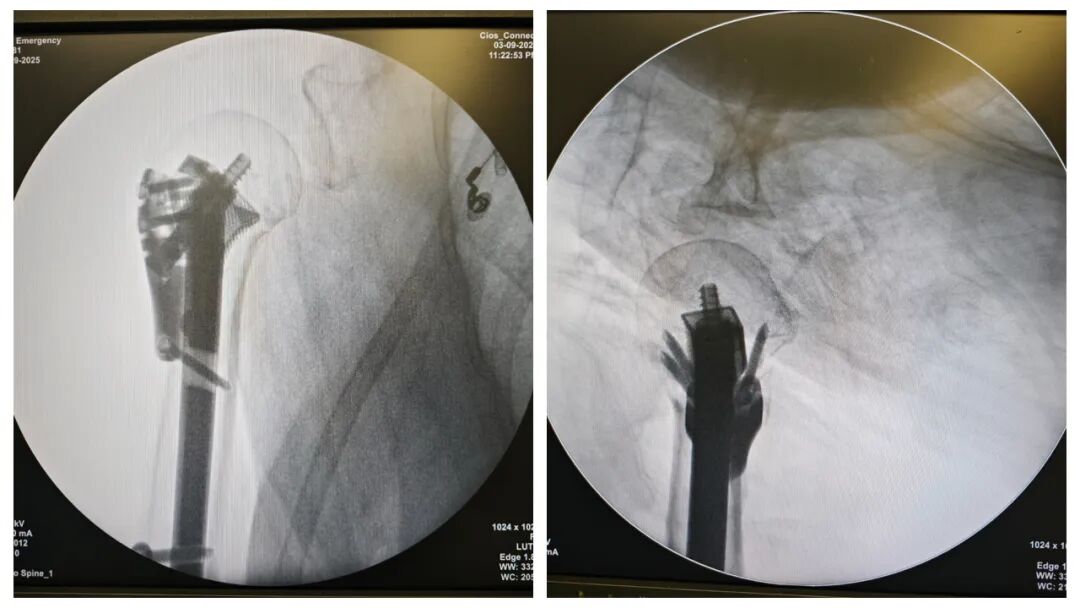

图片

图2  患者术前三维CT

该患者为年龄接近80岁的女性,不慎摔倒后,导致肱骨近端骨折,更加棘手的是该患者患有严重骨质疏松,骨组织如同“蛋壳样”,骨皮质薄弱、肱骨头空虚。传统钢板需要大量植骨支撑或者腓骨条等作为支撑,术后为了避免固定失效,术后需要限制活动1月甚至3月,患者急切想回归正常生活。刘国辉主任及夏天教授团队充分考虑患者高龄及严重骨质疏松的特殊情况,通过研读影像资料,患者病情比较适合“解剖髓内支撑重建系统”这一先进术式。通过和患者的沟通,最终决定采用个性化内植物定制的“解剖髓内支撑重建系统”。